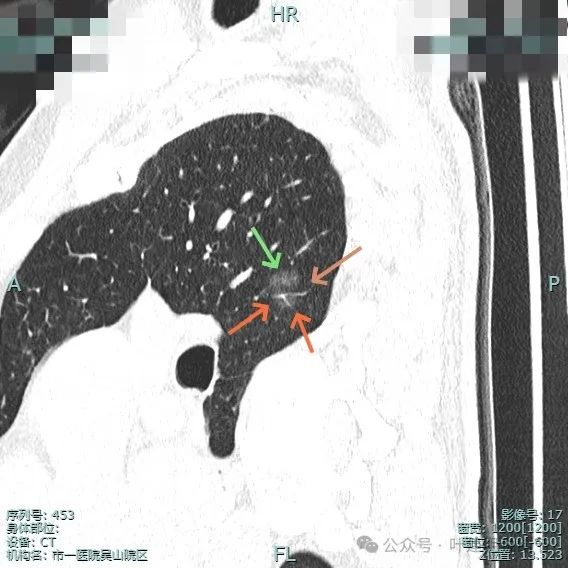

再来看主病灶右上叶后段病灶6的靶重建影像:

病灶磨玻璃密度,未见明显实性成分,但有血管进入。

血管穿行明显,表面有毛刺征,灶内有空泡征。

分叶明显,灶内点状高密度(血管穿行)表面有细小毛刺征。

灶内密度略显不均,有空泡征,表面有毛刺征。

毛刺与血管进入,整体是纯磨,轮廓与边界清。

少许毛刺,整体轮廓清。

血管穿行并发现细小分支的样子,表面不平有细毛刺,灶内有小空泡征。

血管穿行并略有增粗,表面不平有浅分叶,整体轮廓与边界清。

血管进入并有发出分支,边缘有细毛刺,表面不光滑,整体轮廓清,瘤肺边界清楚。

主病灶术前定位,医用胶就在病灶边上(上图绿色的是定位医用胶,红色箭头指的是病灶6)。